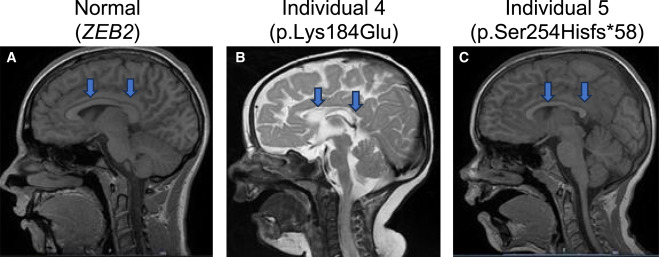

Fig. 1 Brain MRI shows corpus callosum hypoplasia in two affected individuals with TMEM184B variants (A) Sagittal plane of spoiled gradient recalled acquisition (SPGR) magnetic resonance imaging (MRI) in an individual of the same age as individual 5 (family 5-II-1) who has an unrelated pathogenic variant (ZEB2) and shows no alterations in corpus callosum thickness. (B) Sagittal T2 MRI in individual 4 (family 4-II-1; p.Lys184Glu) shows corpus callosum disruption. (C) Sagittal SPGR MRI in individual 5 (family 5-II-1; c.787+1G>A) shows corpus callosum hypoplasia.